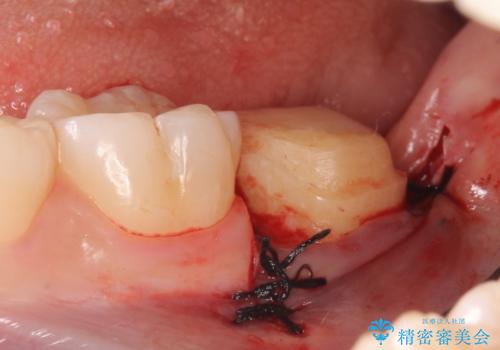

- 左下7の銀歯を白くしたいといらっしゃった方の症例です。

左下7遠心(下記のX線写真の左側)の歯質が歯肉縁下でかつポケットも深かったため、歯茎を下げる歯周外科を行いました。

その後歯茎の治りを待ちポケットが正常値であることを確認後、オールセラミッククラウンによる補綴を行いました。